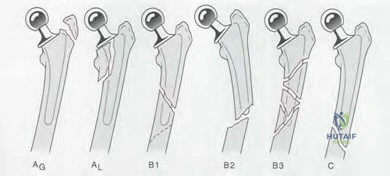

In planning a revision total hip arthroplasty, the surgeon evaluates the femoral bone stock. There is complete loss of metaphyseal cancellous bone, and diaphyseal bone loss extends 2 cm distal to the lesser trochanter. However, the diaphyseal isthmus remains intact with 5 cm of scratch fit available. What is the correct Paprosky Femoral classification and the most appropriate reconstructive strategy?

Question 31

A 75-year-old male requires a revision THA. Preoperative radiographs reveal a loose femoral stem with severe diaphyseal bone loss, a completely absent isthmus, and less than 4 cm of intact diaphyseal bone for distal fixation.

A 68-year-old male presents with aseptic loosening of a THA. Radiographs show a Paprosky Type IIIB femoral defect. The femoral isthmus has approximately 1.5 cm of diaphyseal scratch fit available. What is the most appropriate femoral revision strategy?